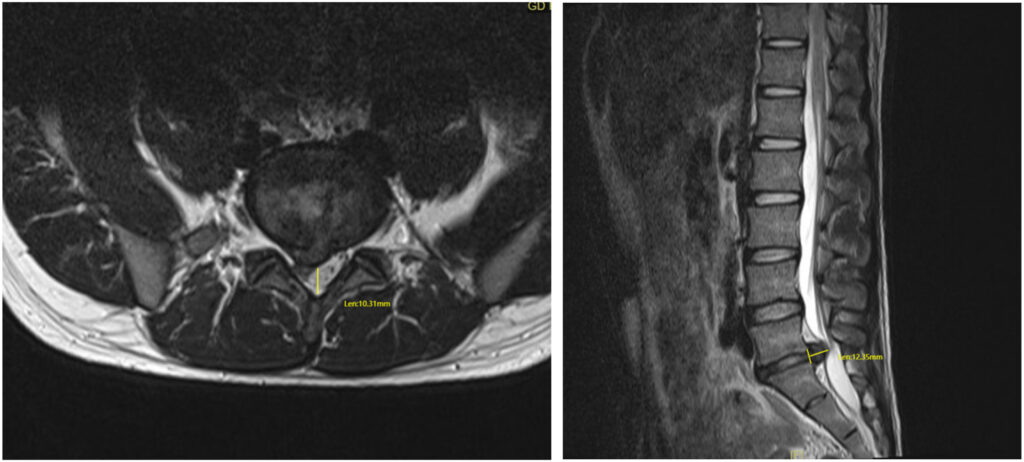

- MRI scans are the most effective tool for visualising disc bulges and assessing whether nearby nerves are being compressed or whether there are associated annular tears.